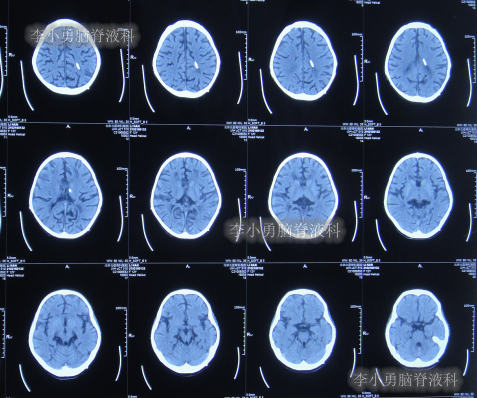

住院治疗第28天即2014年4月14日,复查头颅CT示幕上脑室大小恢复到基本正常的状态,第四脑室再度显著缩小但仍稍大(图-11)。

图-11:2014年4月14日头颅CT

住院治疗第30天即2014年4月16日,查头颅CT示幕上和第四脑室均基本正常(图-13)。

图-13:2014年4月16日